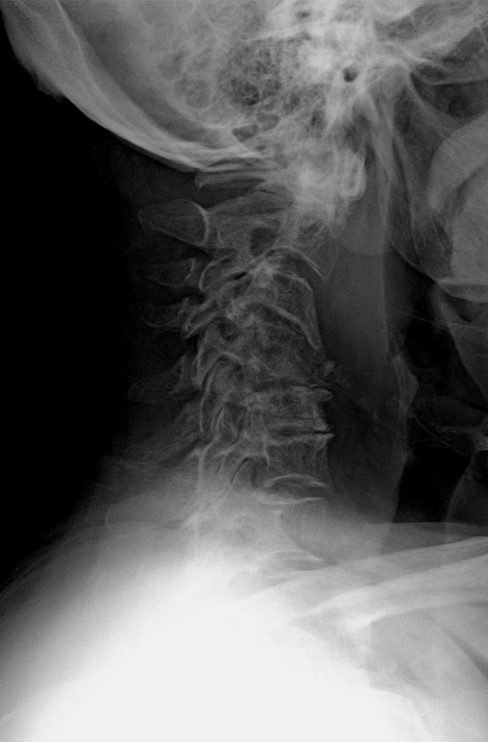

Ameliyat Öncesi